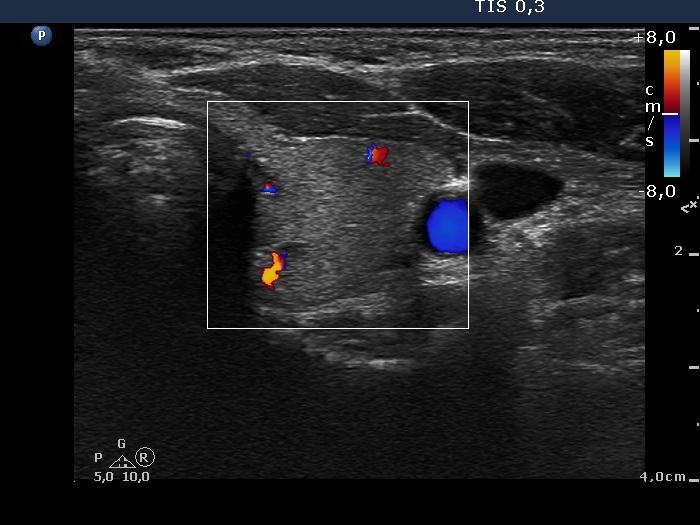

Initial examination (first row of images):

Clinical presentation: A 39-year-old woman was referred for evaluation of neck complaints lasting for more than a month. The patient had fever, neck pain. She has got two courses of antibiotics and non-steroid anti inflammatory drugs which had no effect.

Palpation: The right lobe was painful and hard while the left lobe was tender.

Laboratory examination: TSH 0.01 mIU/L, FT4 29.1 pM/L, FT3 7.45 pM/L, CRP 31.2 mg/L.

Ultrasonography: The thyroid presented with hypoechoic areas which had blurred borders. The echogenicity index was approximately 65% in the right and 20% in the left lobe. The thyroid was almost completely avascular.

Diagnosis: subacute, granulomatous de Quervain's thyroiditis.

Suggestion. Steroid therapy was suggested.